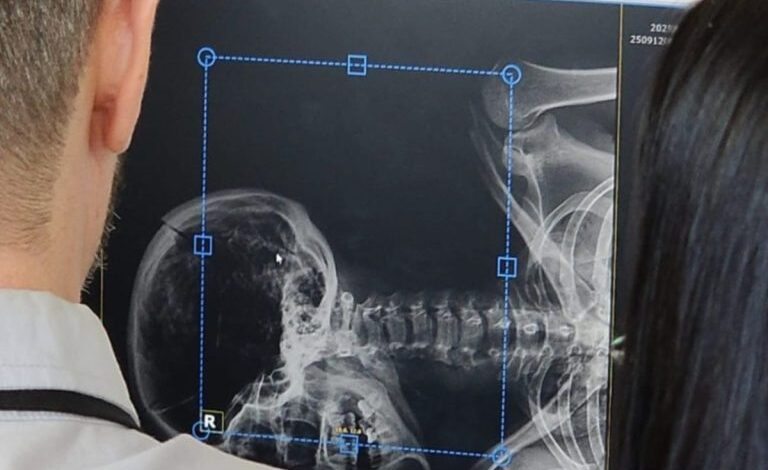

O Instituto-Geral de Perícias (IGP) anunciou a implementação de cinco unidades do scanner cadavérico Flatscan, que passam a ser utilizados…

O Instituto-Geral de Perícias (IGP) recebeu 50 novos equipamentos de última geração que vão reforçar o trabalho de identificação de…